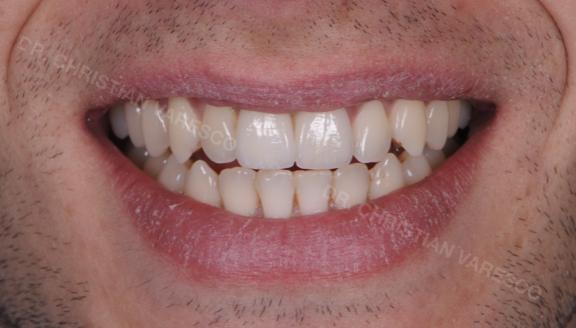

Caso clinico 1:

Situazione iniziale:

il paziente ha perso l’incisivo centrale di destra dopo una brutta caduta sugli sci.

Trattamento eseguito:

viene inserito un impianto dentale dove manca il dente. L’intervento dura circa 30 minuti e con una buona anestesia locale risulta totalmente indolore. Il paziente può ritornare così a sorridere e a mordere la vita!

Il paziente dopo lo shock iniziale ritrova l’estetica e la sicurezza di sorridere di nuovo. L’immagine di colore grigio mostra come appare un impianto in radiografia.